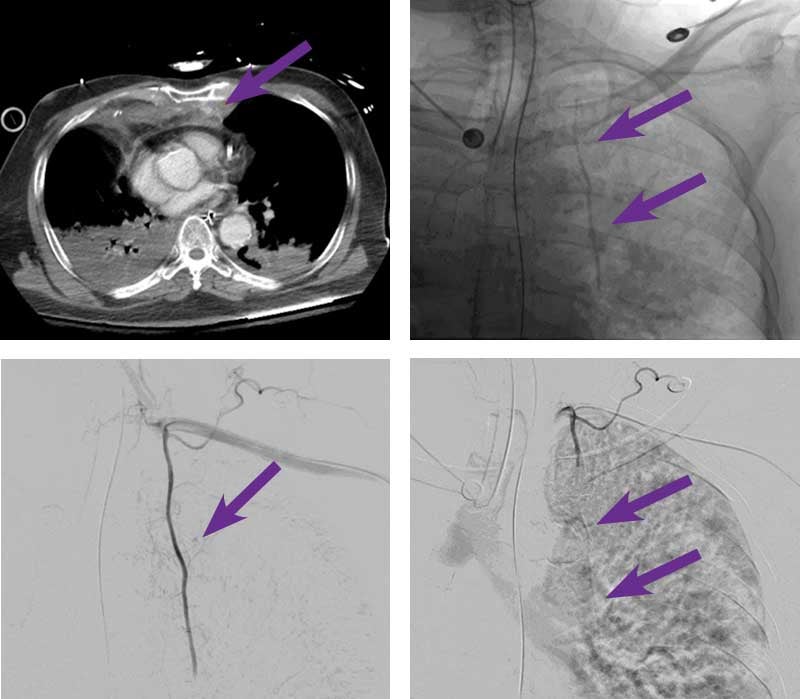

84-year-old male with lung cancer, stage 3b (dx 2021) & type 2 diabetes presented after cardiac arrest. In the ER, he was hypotensive, started on pressor support and admitted to the ICU. CT angiogram of the chest revealed active hemorrhage in the substernal area from the left internal mammary artery.

Intervention used

Scan images from Obsidio internal mammary artery embolization case.